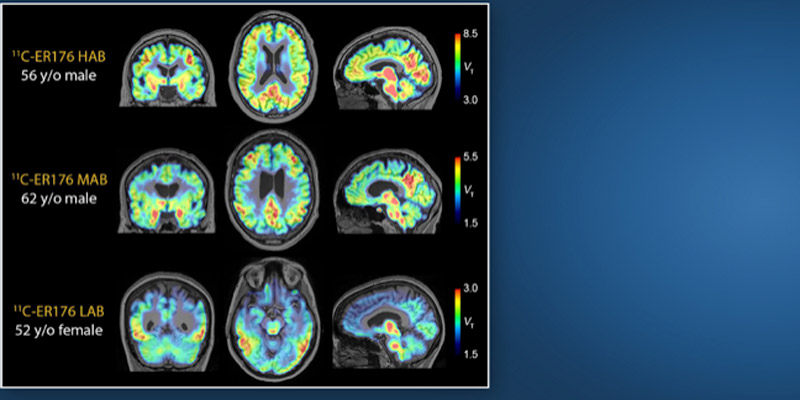

El liderazgo del Hospital Houston Methodist en esta área queda de manifiesto en el desarrollo innovador de tecnología de imagen PET, en particular con el uso del nuevo trazador PET 11C-ER176.

A diferencia de otros trazadores PET, el 11C-ER176 permite observar la inflamación de forma eficaz en todos los tipos genéticos de pacientes.

Este trazador actúa sobre la proteína TSPO, un marcador de inflamación, lo que permite a los científicos obtener imágenes detalladas incluso en personas que antes no podían ser evaluadas debido a su perfil genético.

Además, la vida media corta del Carbono 11, el isótopo utilizado en el 11C-ER176, reduce considerablemente la exposición a la radiación en los pacientes.